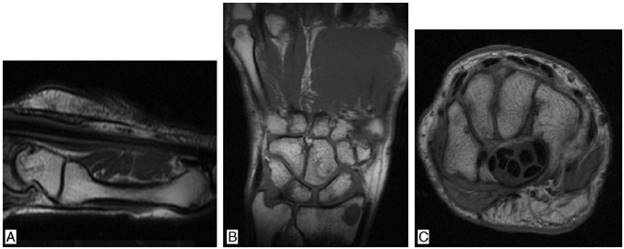

It is a 38-year-old man who in 2011 presented nephrotic syndrome and arterial hypertension, and was taken to kidney biopsy, which documented C1q nephropathy. The patient received treatment with 6 monthly boluses of cyclophosphamide and subsequently was changed to azathioprine, presenting gastrointestinal intolerance to the latter drug, and for this reason was changed to mycophenolate, with adequate control of the nephropathy. Systemic lupus erythematosus (SLE) was ruled out, since the patient did not present clinical stigmata of this disease and the immunological studies were normal (negative ANAS, ENAS and anti-DNA, normal complement, negative lupus anticoagulant, anticardiolipins and B2 glycoprotein). Three years after the onset of the nephropathy, presents arthralgias on hands of inflammatory characteristics, associated with episodes of synovitis and morning stiffness during 40 min. Physical examination shows synovitis and pain in 10 joints (bilateral 2-5 PIP and wrists) (Fig. 1). Laboratory data are collected finding: ESR 67mm/h, CRP 25.7mg/dl (normal between 0 and 1 mg/dl), positive high titer of anti-cyclic citrullinated peptide (anti-CCP) (98.9 mg/dl, normal value up to 20 mg/dl), high positive rheumatoid factor (89.7 mg/dl, normal value up to 14 mg/dl). Given the history of nephropathy and the establishment of a clinical picture of inflammatory arthropathy, studies were extended in order to rule out SLE. Samples were taken for ANAS, ENAS, anti-DNA, IgG and IgG antiocardiolipin antibodies, IgG and IgM antibeta2 glycoprotein antibodies and VDRL, all with negative results, as well as normal complement. The nuclear magnetic resonance showed in the right hand cortical erosions in all bones of the carpus and distal radius as well as in the head of the 2nd, 3rd and 5th metacarpal bones, with incipient synovitis in metacarpophalangeal joints of the 1st, 2nd, 3rd and 4th fingers. In the left hand there were mild periarticular synovial inflammatory changes of the carpus with mild thickening of the periarticular synovial, both dorsal and ventral, with incipient generalized synovitis in metacarpophalangeal joints (Fig. 2). Since there was not any clinical or paraclinical finding that would suggest the presence of SLE and in the presence of highly positive acute-phase reactants, anti-CCP and rheumatoid factor, it was made the diagnosis of rheumatoid arthritis (RA), deciding to optimize its immunomodulatory management with methotrexate 15 mg every week, with which the patient presents adequate control of his joint symptoms and enters into clinical remission of RA.

Fig. 2 Axial section. Note the cortical erosions in all bones of the carpus and distal radius as well as in the head of the 5th metacarpal bone.